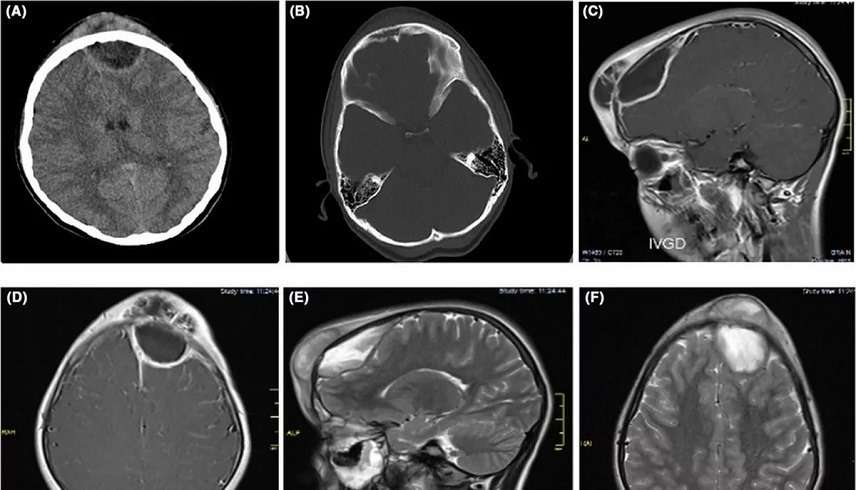

وأشار الأطباء في إيران إلى أن الكتلة كانت "قاسية" و"لامعة" و"مؤلمة عند اللمس".. وأظهرت عمليات المسح أن الكتلة، التي نمت منذ ذلك الحين إلى حجم كرة التنس تقريباً، كانت مدفونة في الفص الجبهي، وهو جزء من الدماغ مسؤول عن الذاكرة والعواطف.

وشخّص الأطباء إصابة الفتاة بورم وعاء منتفخ، وهو من المضاعفات النادرة ولكن الخطيرة لالتهاب الجيوب الأنفية أو عدوى الجيوب الأنفية.. ويحدث ذلك عندما يتراكم السائل المعدي في الجبهة.

وأُعطيت الفتاة جرعة كبيرة من المضادات الحيوية بعد إزالة الكتلة الموجودة على جبينها من العدوى أثناء الجراحة، والتي تم فيها إزالة شريحة عظمية مؤقتاً من الجمجمة للوصول إلى الدماغ.. وبعد ستة أشهر من العملية الكبرى، لم تظهر الكتلة مرة أخرى، وقد أعطى الأطباء للطفلة شهادة صحية تفيد بخلوها من المرض، بحسب صحيفة ميرور البريطانية.